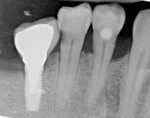

Horizontal distance from the implant platform/abutment connection to the adjacent tooth: The data indicates that as the distance between the natural tooth and the implant increases, the incidence of decay increases precipitously (Figure 2 and Figure 3). Decay occurrences range from 7.4% when the implant-tooth distance (ITD) is <2 mm to 40% when the ITD is ≥6 mm. In the 69 sites that exhibited caries, the mean ITD was 4.1 mm, and in the 338 sites without decay the mean ITD was 3.5 mm (P = .005) (Table 1). A logistic regression was performed with the single binary variable indicating whether or not the "horizontal threshold distance" was greater than 4 mm. The results show a statistically significant odds ratio of 2.00 (95% confidence interval of 1.191599, 3.350288) (Table 2.) Therefore, it is suggested that the horizontal threshold of 4 mm be considered as the "critical ITD."

Presence or absence of restorations on the adjacent teeth: A positive correlation between existence of a previous restoration and decay was found (Figure 4, Figure 5, and Table 2).